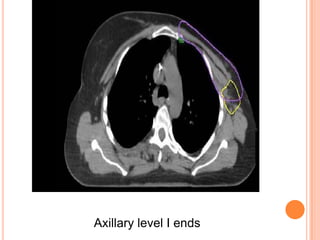

Axillary level I ends